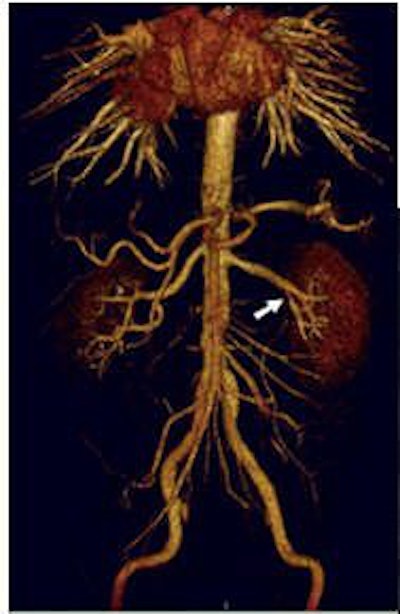

![]() |

| Targeted MIP (20 mm) from same patient as above. By applying parallel acquisition with an acceleration factor of 3, the 3D dataset was acquired with 0.8 x 0.7 x 0.9 mm³ voxels over a 420-mm field-of-view, during a 19-second breath-hold. Note the branch stenosis at the origin of the left inferior pole renal artery. |